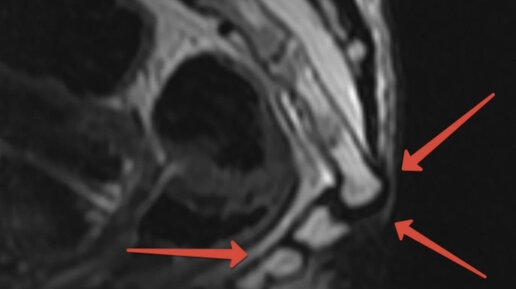

Привет из 90х 🤚🙈 Катались на горках с картонками или пленкой ? 🛷🛷Возможно у тебя так же 😳😬 Это мой сломанный копчик 30ти летней давности 👆 Как сейчас помню эту жуткую пронизывающую боль после неудачного приземления на пятую точку во время покатушек с горки на картонке 🥹 Если честно я еще будучи ребенком понимала что у меня перелом , но факт того что я шла домой своими двумя ногами меня путал . « Ведь если бы я сломала позвоночник я б не смогла ходить ? 🙄» Вполне логично для моего детского возраста на тот момент так рассуждать ...